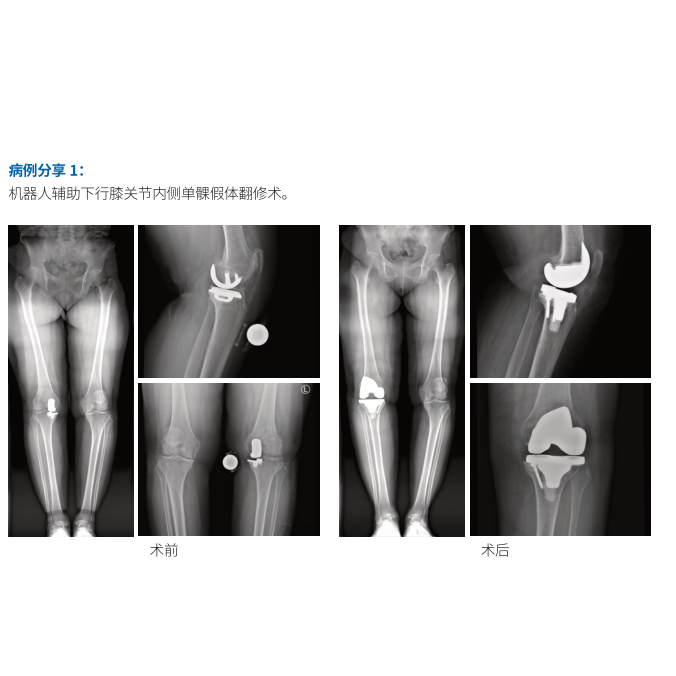

产品名称:三位一体关节置换手术机器人

产品地位:获批 UKA/TKA 注册证的国产关节机器人